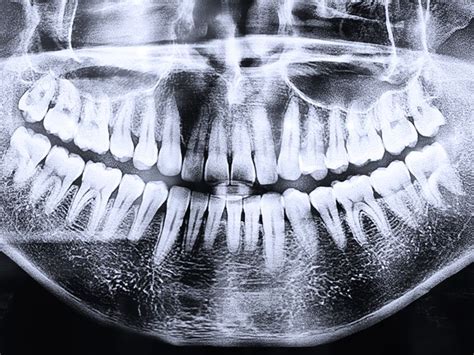

Además, las radiografías panorámicas son esenciales a la hora de diagnosticar problemas dentales de cara a una ortodoncia. Mediante ellas, el ortodoncista busca posibles patologías, observa la posición y forma de dientes y mandíbulas y puede preparar un correcto tratamiento.

- Panorámicas: Ofrecen una visión completa de los dientes, maxilares y mandíbula en una sola imagen.

- Radiografías panorámicas y teleradiografías: La primera permite ver los dientes de la boca de frente. La segunda permite ver la cabeza de lado.

En otras palabras, podemos decir que esta es una radiografía del perfil del paciente. Sirve para estudiar las proporciones del cráneo y determinar si son las adecuadas. Es una radiografía frontal, en la que se obtiene una imagen general de los dientes y los huesos maxilares (maxilar superior y mandíbula).